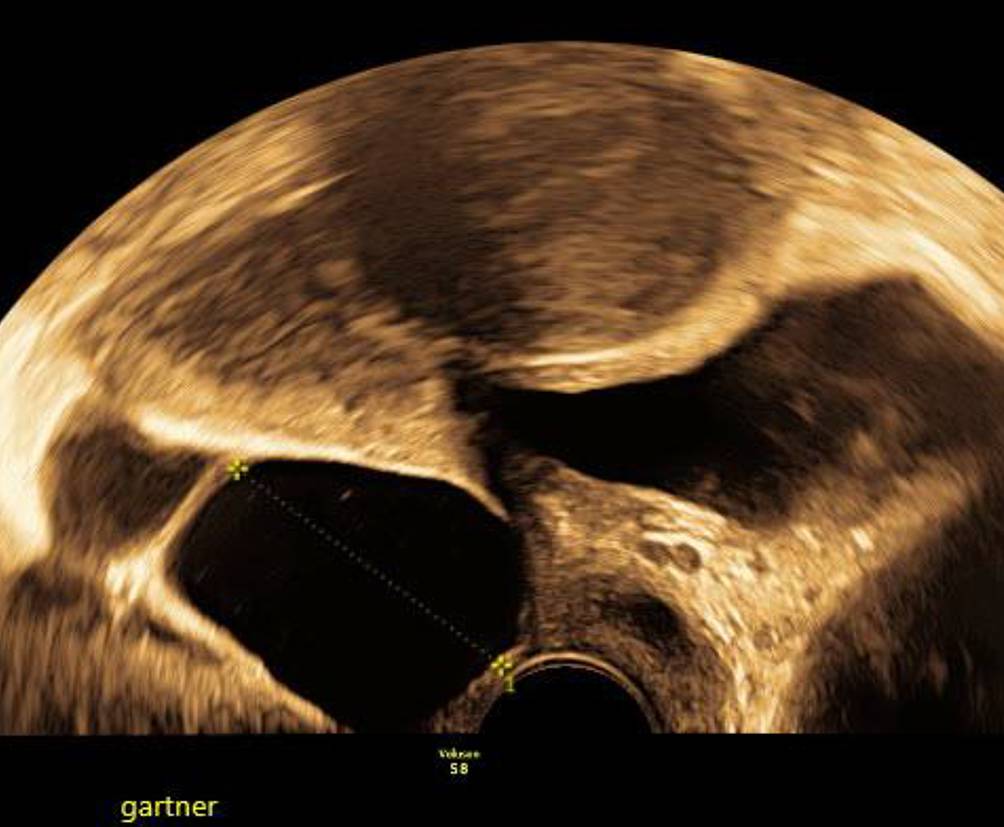

Abb. 6

Über Jahre konstante Gartner-Gang-Zyste, die trotz der unmittelbaren Nähe zur Blase der Patientin nie Beschwerden machte

Die Gartner-Gang-Zyste

Gartner-Gang-Zysten sind im Prinzip harmlos, das Innere der Zysten ist meist dünnflüssig, kann aber auch gallertartige Konsistenz haben [4]. Selten – und dann eher im jugendlichen Alter – können sie sehr groß werden [5]. Es gibt einzelne Fallberichte von malignen Prozessen im Vaginalbereich, die aus Gartner-Gang-Zysten entstanden sein sollen [6, 7]. Beobachten mittels Bildgebung ist bei symptomlosen Patientinnen einer Punktion oder Exzision auf jeden Fall vorzuziehen (Abb. 5 und 6).